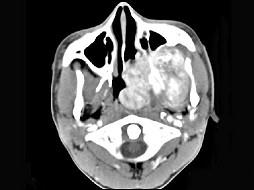

男性,19岁,左侧鼻腔反复出血一年余,CT、MRI扫描如图所示,请选择最可能诊断 ( )

答案: E